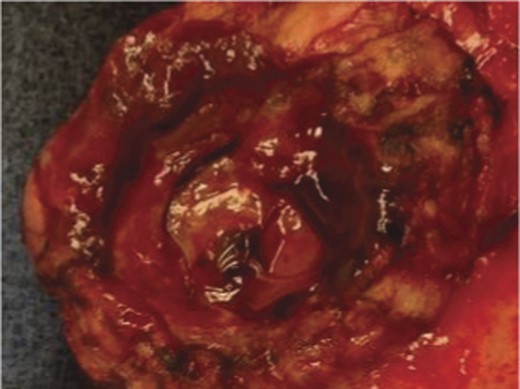

A frail 77-year-old multiparous Caucasian female with a history of aspirin and naproxen use, presented to an outside hospital with epigastric pain and an episode of hematemesis. She had no prior history of peptic ulcer disease, alcoholism or pancreatitis. The patient was hemodynamically stable with an acute anemia (hemoglobin of 7.7 g/dl), which prompted transfusion of 2 units of PRBC and transfer to a tertiary care facility. Upon transfer, she underwent an emergent upper endoscopy, which revealed a large amount of blood with clots in the lumen of the stomach. However, sufficient suctioning of the large intra-gastric clots was not possible; hence, an underlying etiology was not obtainable. The patient subsequently underwent a diagnostic angiography, which revealed a 4 cm mid-SA pseudoaneurysm with active contrast extravasation into the stomach which can be seen in Figs 1 and 2. The radiologist decided to perform a transcatheter arterial coil embolization of the artery to halt the active bleeding. A post procedure angiography revealed no further contrast extravasation. A planned upper endoscopy was repeated the following day that revealed some residual clotted blood in the stomach, no active bleeding and a deep 4 cm gastric ulcer. Due to the high risk of re-bleeding, the patient was optimized physiologically and consented and prepared for exploration. Intraoperatively we observed that the SA pseudoaneurysm was densely adherent to the posterior wall of the stomach, and coursing through an inflamed distal pancreas. We decided to proceed with an en bloc resection of SA pseudoaneurysm, distal pancreatectomy, partial gastrectomy and splenectomy. After the celiac axis was surgically defined, proximal and distal SA controls were obtained and a circumferential posterior gastrotomy was made. There was a visible posterior gastric mucosa to splenic arterial fistula, with the radiologically inserted embolic coils clearly visible. This can be seen in surgical specimen (Figs 3 and 4). Once the stomach was reflected, the splenic vessels and the pancreas were divided and the specimen removed. The pathology reports indicated active gastritis with transmural ulceration into the splenic artery (SA) and adjacent pancreatic tissue. No malignant cells were identified in the gastric or pancreatic tissue and the SA was not aneurysmal (Fig. 5). During the postoperative period, the patient had an uncomplicated recovery and was discharged on day 5.

Pathologic specimen–Gastro–splenic artery fistula. Normal caliber splenic artery.